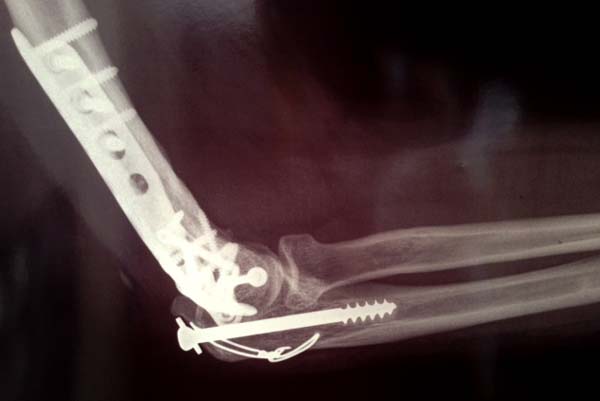

Примеры: первому более 15 лет фиксирован шурупом и tension band

technique, а второй перелом открытый больной 80 лет, после наружного

фиксатора в первом этапе и окончательная фиксация вторично. Третьий раз

внесуставная остеотомия...

Имя     : 1-1 old humerus distal.jpg

Тип     : image/jpeg

Размер  : 50262 байтов

Имя     : 1-2 old humerus distal.JPG

Размер  : 48833 байтов

Имя     : 1-3 old humerus distal.JPG

Размер  : 31506 байтов